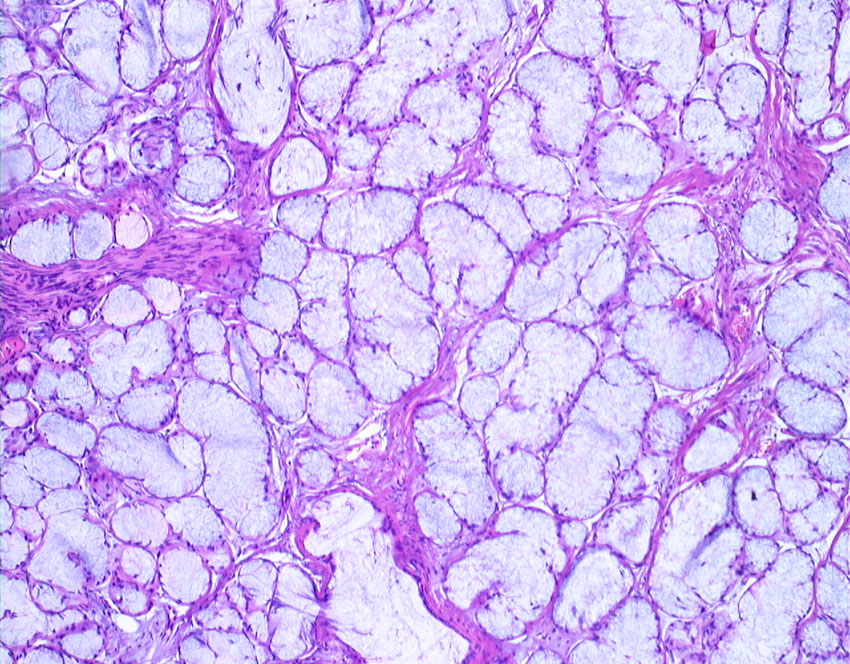

左上の写真で見えるのは,腫瘍内部にあった小脳組織です。内胚葉,外胚葉性組織など多様に分化した組織が混入しています。